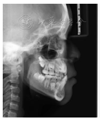

头颅侧位片示:下颌相对颅底位置靠前,趋向Ⅲ类错

,上下切牙舌腭向倾斜,骨龄CS1起始期。

患者治疗前头影测量分析结果

| 北京大学分析法 | ||||

|---|---|---|---|---|

| 测量结果 | 测量值 | 正常值 | 标准差 | 诊断提示 |

| 骨测量 | ||||

| SNA | 84.5° | 82.3 | 3.5 | 上颌相对颅底位置正常 |

| SNB | 81.9° | 77.6 | 2.9 | 下颌相对颅底位置靠前 |

| ANB | 2.6° | 4.7 | 1.4 | 趋向Ⅲ类错![]() |

| FH-NPo | 87.4° | 83.1 | 3 | 颏部前突 |

| NA-Apo | 2.9° | 10.3 | 3.2 | 上颌相对面部后缩 |

| FMA | 28.1° | 31.8 | 4.4 | 均角型 |

| SGn-FH | 62.1° | 65.5 | 2.9 | 聚合生长型,颏部前突 |

| MP-SN- | 32.5° | 35.8 | 3.6 | 下颌提陡度、面部高度适宜 |

| Po-NB | 2mm | 0.2 | 1.3 | 颏部发育量较大,颏部前突 |

| 牙测量 | ||||

| U1-NA | -1.2mm | 3.1 | 1.6 | 上中切牙后缩 |

| U1-NA | 7° | 22.4 | 5.2 | 上中切牙腭向倾斜 |

| L1-NB | 3.5mm | 6 | 1.5 | 下中切牙后缩 |

| L1-NB | 19.4° | 32.7 | 5 | 下中切牙舌向倾斜 |

| U1-L1 | 151.1° | 122 | 6 | 上下前部牙弓突度较小 |

| U1-SN | 91.5° | 104.8 | 5.3 | 下中切牙相对前颅底平面舌向倾斜 |

| IMPA | 85.1° | 94.7 | 5.2 | 下中切牙相对下颌平面舌向倾斜 |